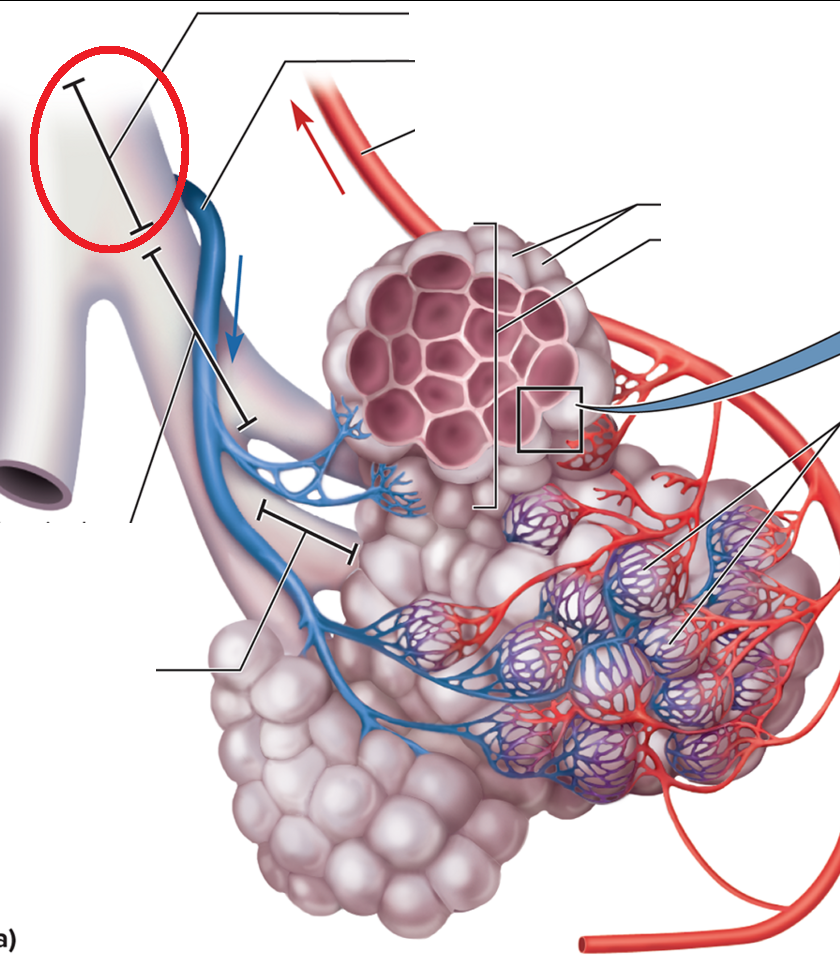

Terminal bronchiole BT

resp bronchiole

Alveolar duct BT

Alveolar sac BT

Alveolus BT